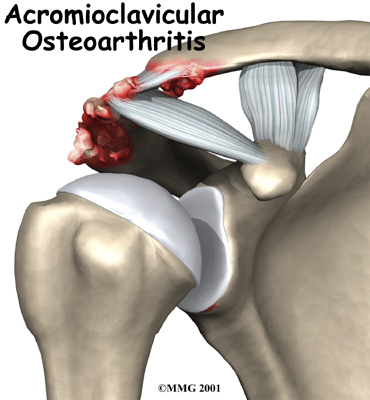

Some joints in the body are more likely to develop problems from normal wear and tear. Degeneration causes the cartilage that cushions the joint to wear out. This type of arthritis is called osteoarthritis. Doctors sometimes refer to this type of arthritis as arthrosis.

The acromioclavicular (AC) joint in the shoulder is a common spot for osteoarthritis to develop in middle age. Degeneration of the AC joint can be painful and can cause difficulty using the shoulder for everyday activities.

We use our shoulder constantly. The resulting strain makes AC joint osteoarthritis a common disorder. The AC joint is under constant stress as the arm is used overhead. Weightlifters and others who repeatedly lift heavy amounts of weight overhead tend to have an increased incidence of the condition, and often at a younger age.

In its early stages, AC joint osteoarthritis usually causes pain and tenderness in the front of the shoulder around the joint. The pain is often worse when the arm is brought across the chest, since this motion compresses the joint. The pain is vague and may spread to include the shoulder, the front of the chest, and the neck. If the joint has been injured in the past, there may be a bigger bump over the joint on the affected shoulder than on the unaffected shoulder. The joint may also click or snap as it moves.

The most common procedure for AC joint osteoarthritis is resection arthroplasty. A resection arthroplasty involves removing a small portion of the end of the clavicle. This leaves a space between the acromion (the piece of the scapula that meets your shoulder) and the cut end of the clavicle, where the joint used to be. Your surgeon will take care not to remove too much of the end of the clavicle to prevent any damage to the ligaments holding the joint together. Usually only a small portion is removed, less than one cm (about three-eighths of an inch). As your body heals, the joint is replaced by scar tissue. Remember, the AC joint doesn't move much, but it does need to be flexible. The scar tissue allows movement but stops the bone ends from rubbing together.